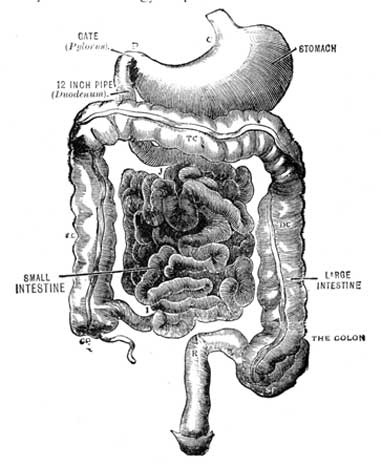

Fig. 1.—A bit of the inner coat of the small intestine.

Fine threads of blood vessels (capillaries) take it up from the stomach and intestines. Also along the intestines there are little projections (villi), through which the food passes into a blood stream leading to the liver, where the blood is then purified. These projections also contain lacteals or little vessels containing blood without its red corpuscles. A duct carries this colourless blood mixed with absorbed food to the left side of the neck, where it empties into the blood stream. These lacteals have a special affinity for the fat of the food. Most of the rest of the food, including the proteid and the carbohydrate or starchy portion now in the form of sugar, passes into the capillaries, and then is led to the liver.

The liver will not let through more sugar than is required, storing it up for future use. It also acts as a careful guardian, by arresting many poisons which would otherwise pass into the general circulation. The liver requires for the proper performance of its functions plenty of pure blood, hence the necessity for fresh air and exercise, that the lungs may work well. The liver is easily influenced by alcoholic beverages, and by getting too hard work to do through eating rich foods. A consideration of this delicate and intricate process, whereby the digested food is absorbed, will show that badly-digested food can not hope to be well assimilated, consequently attention should be paid to the quantity and quality of the food we eat (see Digestion; Diet).

Fig. 2.—Two villi containing lacteals. The white canals are lacteals, the darker lines indicate blood vessels (capillaries). Magnified 100 diameters.

(From "Quain's Anatomy.")

Interior of small intestine.